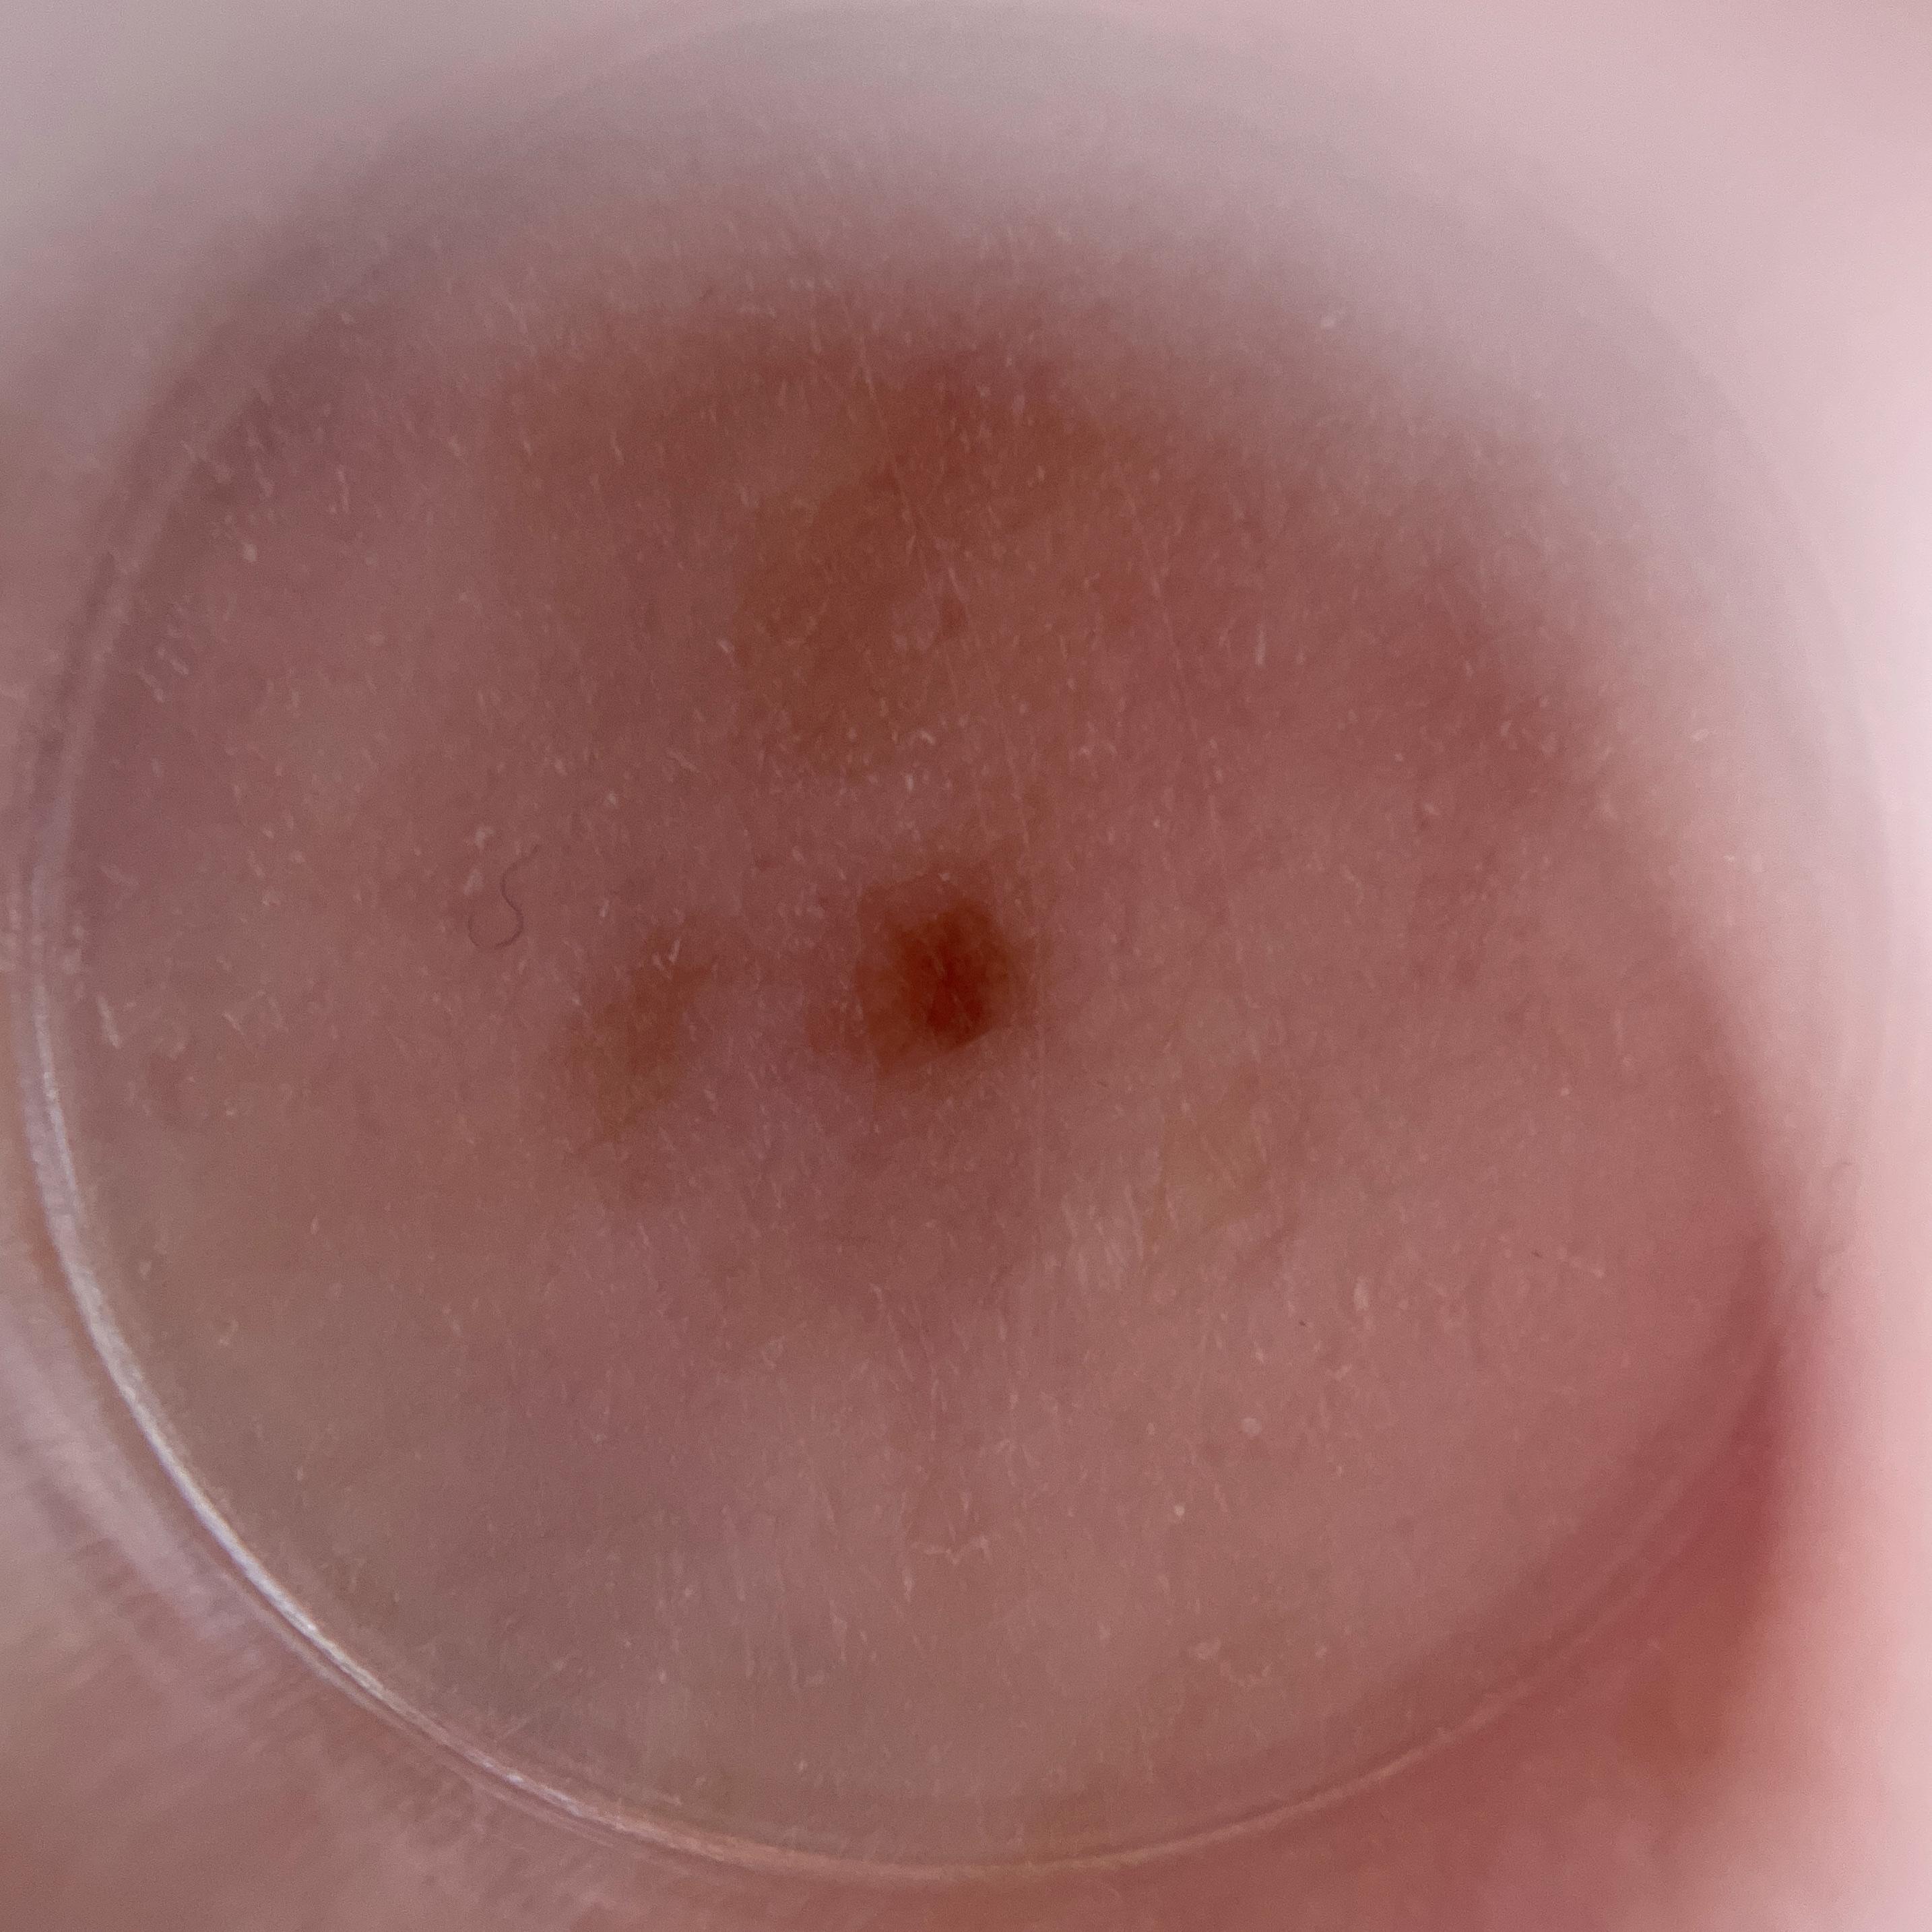

ISIC_9879700

1550 x 1550

Field Value

acquisition_day 497

age_approx 60

anatom_site_1 Upper extremity

anatom_site_general upper extremity

concomitant_biopsy False

diagnosis_1 Benign

diagnosis_confirm_type single image expert consensus

family_hx_mm True

image_manipulation instrument only

image_type dermoscopic

lesion_id IL_5865491

patient_id IP_6745773

personal_hx_mm True

sex female